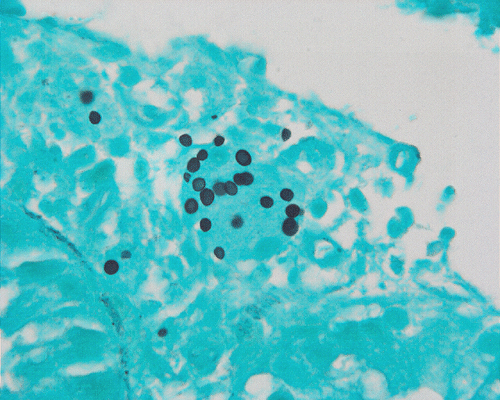

GMS

On low-magnification, the biopsy appears to be a piece of colonic mucosa without evidence of necrosis, erosion, or ulcer (Panel A). On medium-magnification, the lamina contains some vaguely formed collections of large cells (Ú in Panel B). On high-magnification, there are many large, round cells with eccentric nuclei. These are macrophages in clusters that are consistent with granulomas.  Many small, grayish to basophilic, vesicle-like structures are present in the cytoplasm (Panel in C). In other areas, these large, round cells do not really form small clusters and are admixed with lymphocytes (Panel D). Again, many small, grayish vesicle-like structures are present in these cells. A grayish to basophilic core is present and is surrounded by halo (Ú in Panel E).  These structures are most suggestive of microorganisms particularly fungus. On periodic acid Schiff (PAS), these vesicles appear bright purple-red (Panel F and G). The basophilic core is also strongly positive for PAS stain (Panel G). These microorganisms appear dark with Gomori methamine silver stain (Panel H and I).

H. capsulatum, like many other fungal organisms, are well demonstrated by periodic acid Schiff (PAS) stain, Gomori’s methamine silver (GMS) stain, and other appropriate stains in tissue. Although the size and shape can suggest Candida species, there is no pseudohyphae formation in H. capsulatum which allows the distinction. They also lack the paired dense capsular thickening as in Pneuocystis carinii. Coccidiodes immitis form large endospores which allow separation from H. capsulatum. [Click here to see a picture of C. immitis with GMS stain]